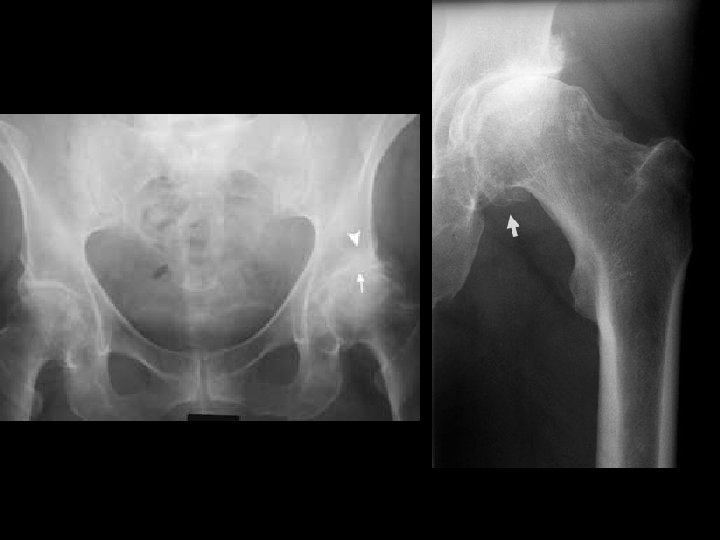

ASSESSMENT • For many plain radiograph remains the best means of assessment: – Evidence of cartilage loss (joint space narrowing) – Bone response (osteophytes and sclerosis) • There is often considerable discordance between structural change and clinical outcome